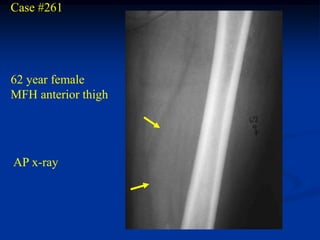

Case #261

62 year female

MFH anterior thigh

AP x-ray

Case #261 62 yearfemale MFH anterior thigh AP x-ray